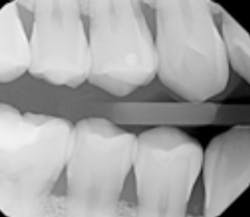

The selection of radiographic images can sometimes change depending on patient conditions, which appears to be the case here. It seems on a first new patient visit, only D0274 bitewing, four radiographic images appeared to be necessary. When the patient returned, it was determined the rest of the D0210 intraoral full series radiographic images were needed. Knowing the specific code's nomenclature/name is the first best step to understanding.

The second step is understanding the D0274 description, which reads, “A radiographic survey of the whole mouth, which usually consists of 14 to 22 periapical and posterior bitewing images intended to display the crowns and roots of all teeth, periapical areas, and alveolar bone.”

This means the bitewings are part of the full series. From a coding and documentation perspective, there are two separate dates of service. Each encounter should be listed for accuracy. For the second date when the full series is documented, a note should be added to the patient record with the date of the bitewings.